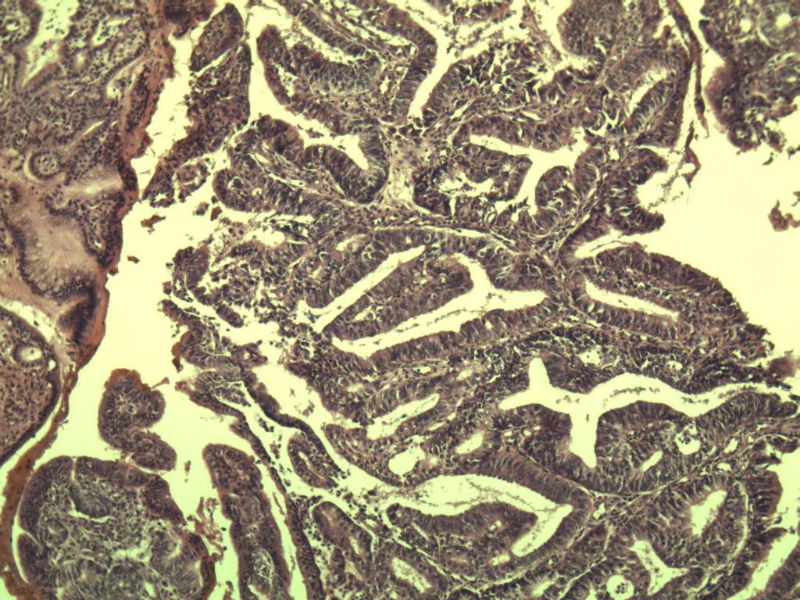

女 32岁 不规则阴道流血 一年  请各位老师看看 谢谢了

遵义医学院附属医院会诊结果    "复杂性增生伴非典型性 "

补充一下病史 病人10个月前因月经不规则行诊刮 诊断非典型性增生  上了曼月乐避孕环(好像是缓慢释放孕激素的那种),         都用激素治疗大半年了 还是这个样子 我还是觉得是癌  只有追踪一下以后病人的情况吧

高分化子宫内膜样癌

非典型复杂性子宫内膜增生,应了解雌孕激素情况。

子宫内膜复杂性非典型性增生,局灶区间质肉芽样(图5)及蜕膜样变,不够癌,建议临床查激素水平并追踪。

从照片看,没看到浸润的地方,我考虑是子宫内膜重度不典型增生。